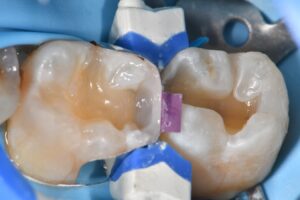

Matrix system: #Garrison Compositight

Substrate adhesive optimization: #Aquacare